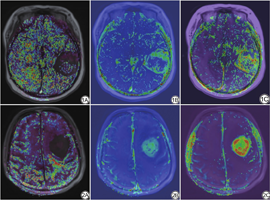

统计结果显示,MGMT非甲基化组的Ktrans值及Ve值明显高于MGMT甲基化组,且差异有统计学意义(P值均<0.05),而两组之间的Kep值差异无统计学意义(P值>0.05;表2,图1、2)。

对于MAP-MRI参数,甲基化组的NG、NGAx、RTOP及RTAP值明显低于非甲基化组(P值均<0.05),而甲基化组的QIV的值明显高于非甲基化组(P=0.033;表3,图3、4)。